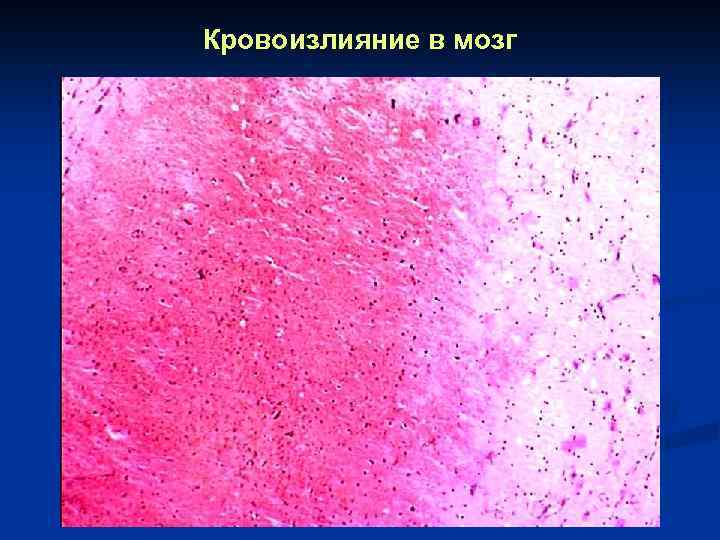

Кровоизлияние в мозг